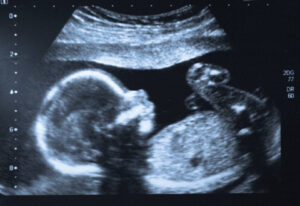

Dr. Widen’s research findings were recently highlighted in an article in The Texas Scientist. Specifically, her work with her colleagues at Columbia University investigating the impacts of mothers’ body weight and the home environment on the development and outcomes of their babies. This research suggests that boys appear to be more vulnerable in utero than girls.

The article, “Boys and Risk in Utero“, has more details about the research and recommendations for women and pregnant people looking to stay healthy.